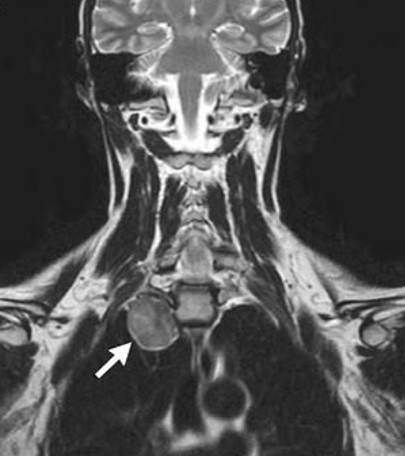

DIAGNOSIS: Harlequin syndrome (HS) due to a thoracic sympathetic ganglion tumor (see radiograph arrow above).

A rare autonomic nervous system disorder, HS is characterized by hemifacial cutaneous sympathetic denervation with consequent anhydrosis and lack of facial rubor on the involved side. Occassionally patients present with a complete Horner's syndrome including myosis, ptosis, and enophthalmos on the affected side. Paradoxically, as in the presented case, there is compensatory flushing and sweating on the unaffected side. The syndrome becomes clinically evident in the setting of exercise, heat and emotional stress. Most cases are primary without demonstrable anatomical abnormalities, or, as in the presented case, may be associated with tumors involving cervical sympathetic ganglions. The syndrome may be congenital, follow sugical interruption of sympathetic pathways, or, rarely, occur in strokes involving the hypothalamus.The treatment in the presented case was surgical, but in most cases it is supportive